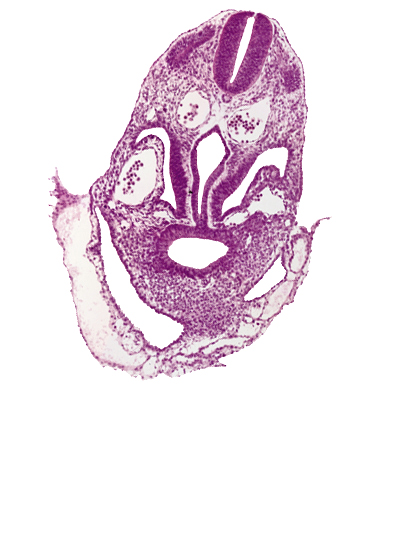

Carnegie Embryo #8943 | Location: 05-02-05

Keywords: amnion, amniotic cavity, caudal part of pericardioperitoneal canal (pleural cavity), dermatomyotome 6 (C-2), extra-embryonic coelom, hepatic antrum, hepatic diverticulum, junction of amnion and umbilical vesicle, junction of foregut and midgut, junction of left horn of sinus venosus and left umbilical vein, pericardial cavity, postcardinal vein, right horn of sinus venosus, umbilical vesicle wall, ventral body wall

Source: The Virtual Human Embryo.